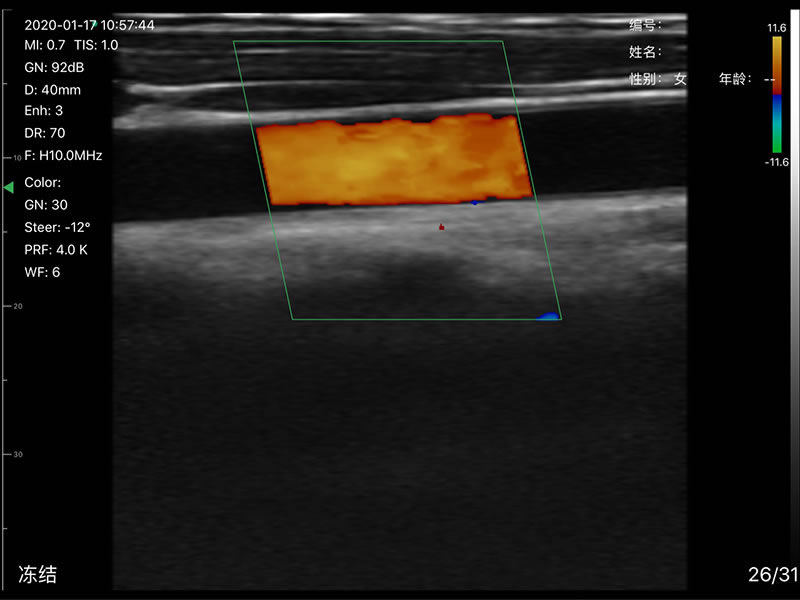

• 探头频率:相控阵2.2/3.6MHz,线阵7.5/10 MHz

• 扫描声头:同时具备微凸、线阵两个声头,并可通过按键快速切换

• 显示模式:B、B/M、Color、PW、PDI

• 穿刺辅助功能:平面内穿刺引导线功能,平面外穿刺引导与血管自动测量功能,针尖显影增强功能